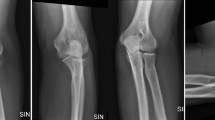

In Group A, 30 cases of fresh Monteggia fractures were included, with an average age of 6.33 ± 2.72 years (range: 1–12 years). The mean follow-up duration was 25.07 ± 10.86 months. There were 22 cases of Bado type I, one case of Bado type II, seven cases of Bado type III, and no cases of Bado type IV. Closed reduction and Kirschner wire internal fixation were performed in seven children, closed reduction and elastic intramedullary nail implantation in nine children, and open reduction with plate internal fixation in 14 children. The average inner-epiphyseal ulna-radius length ratio was 1.091 ± 0.022. The average MEPS score at the last follow-up was 90.67 ± 3.41, the average pronation range was 79.67 ± 1.83, the average supination range was 83.67 ± 2.25, and the average flexion and extension range was 139.33 ± 4.69. All patients achieved excellent radial head reduction.

In Group B, there were 28 cases of chronic Monteggia fracture, with an average age of 7.68 ± 2.9 years (range: 1–14 years) and an average follow-up duration of 17.82 ± 10.50 months. Anterior dislocation of the radial head was observed in 24 cases, anterolateral dislocation in 3 cases, and posterolateral dislocation in 1 case. Twenty-one children underwent debridement of the humeroradial joint cavity, followed by ulna osteotomy and lengthening with plate internal fixation. Seven children received the same procedure, along with Kirschner wire fixation (typical case presented in Figs. 3 and 4). The average inner-epiphyseal ulna-radius length ratio was 1.070 ± 0.027. The average Mayo Elbow Performance Score (MEPS) at the last follow-up was 87.32 ± 7.26, the average pronation range was 71.61 ± 12.84, the average supination range was 77.14 ± 5.52, and the average flexion and extension range was 124.39 ± 12.32. All patients achieved excellent radial head reduction. Outcome parameters for both groups are summarized in Table 1.

The 95% confidence interval for the inner-epiphyseal ulna-radius length ratio was defined as 1.047 to 1.141. Significant differences were observed in radiographic reduction quality, pronation range, supination range, flexion and extension range, and MEPS scores between the normal and abnormal groups (P = 0.002, 0.007, 0.030, 0.045, < 0.001, respectively). We also performed a univariate analysis with Mayo elbow function evaluation as the outcome index. There was no correlation between the Mayo Score and gender, side, fracture type (P > 0.05). The elbow Mayo score in the normal inner-epiphyseal ulna-radius length ratio group was higher than abnormal group (P < 0.05). The elbow Mayo score of the group with injury to surgery time less than 6 months was higher than that of the group with injury to surgery time more than 6 months(P < 0.05) (Table 2). These findings indicate a statistically significant relationship (P < 0.05) between the postoperative inner-epiphyseal ulna-radius length ratio and postoperative imaging reduction quality, pronation range, supination range, flexion and extension range, and MEPS score.